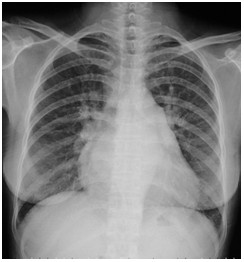

临床执业助理医师实践技能第一考站【X线-肺炎】影像诊断模拟题

2022-03-29